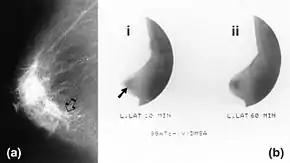

Mammography (left) and DMSA scintimammography (right) images of 4.5cm breast carcinoma | |